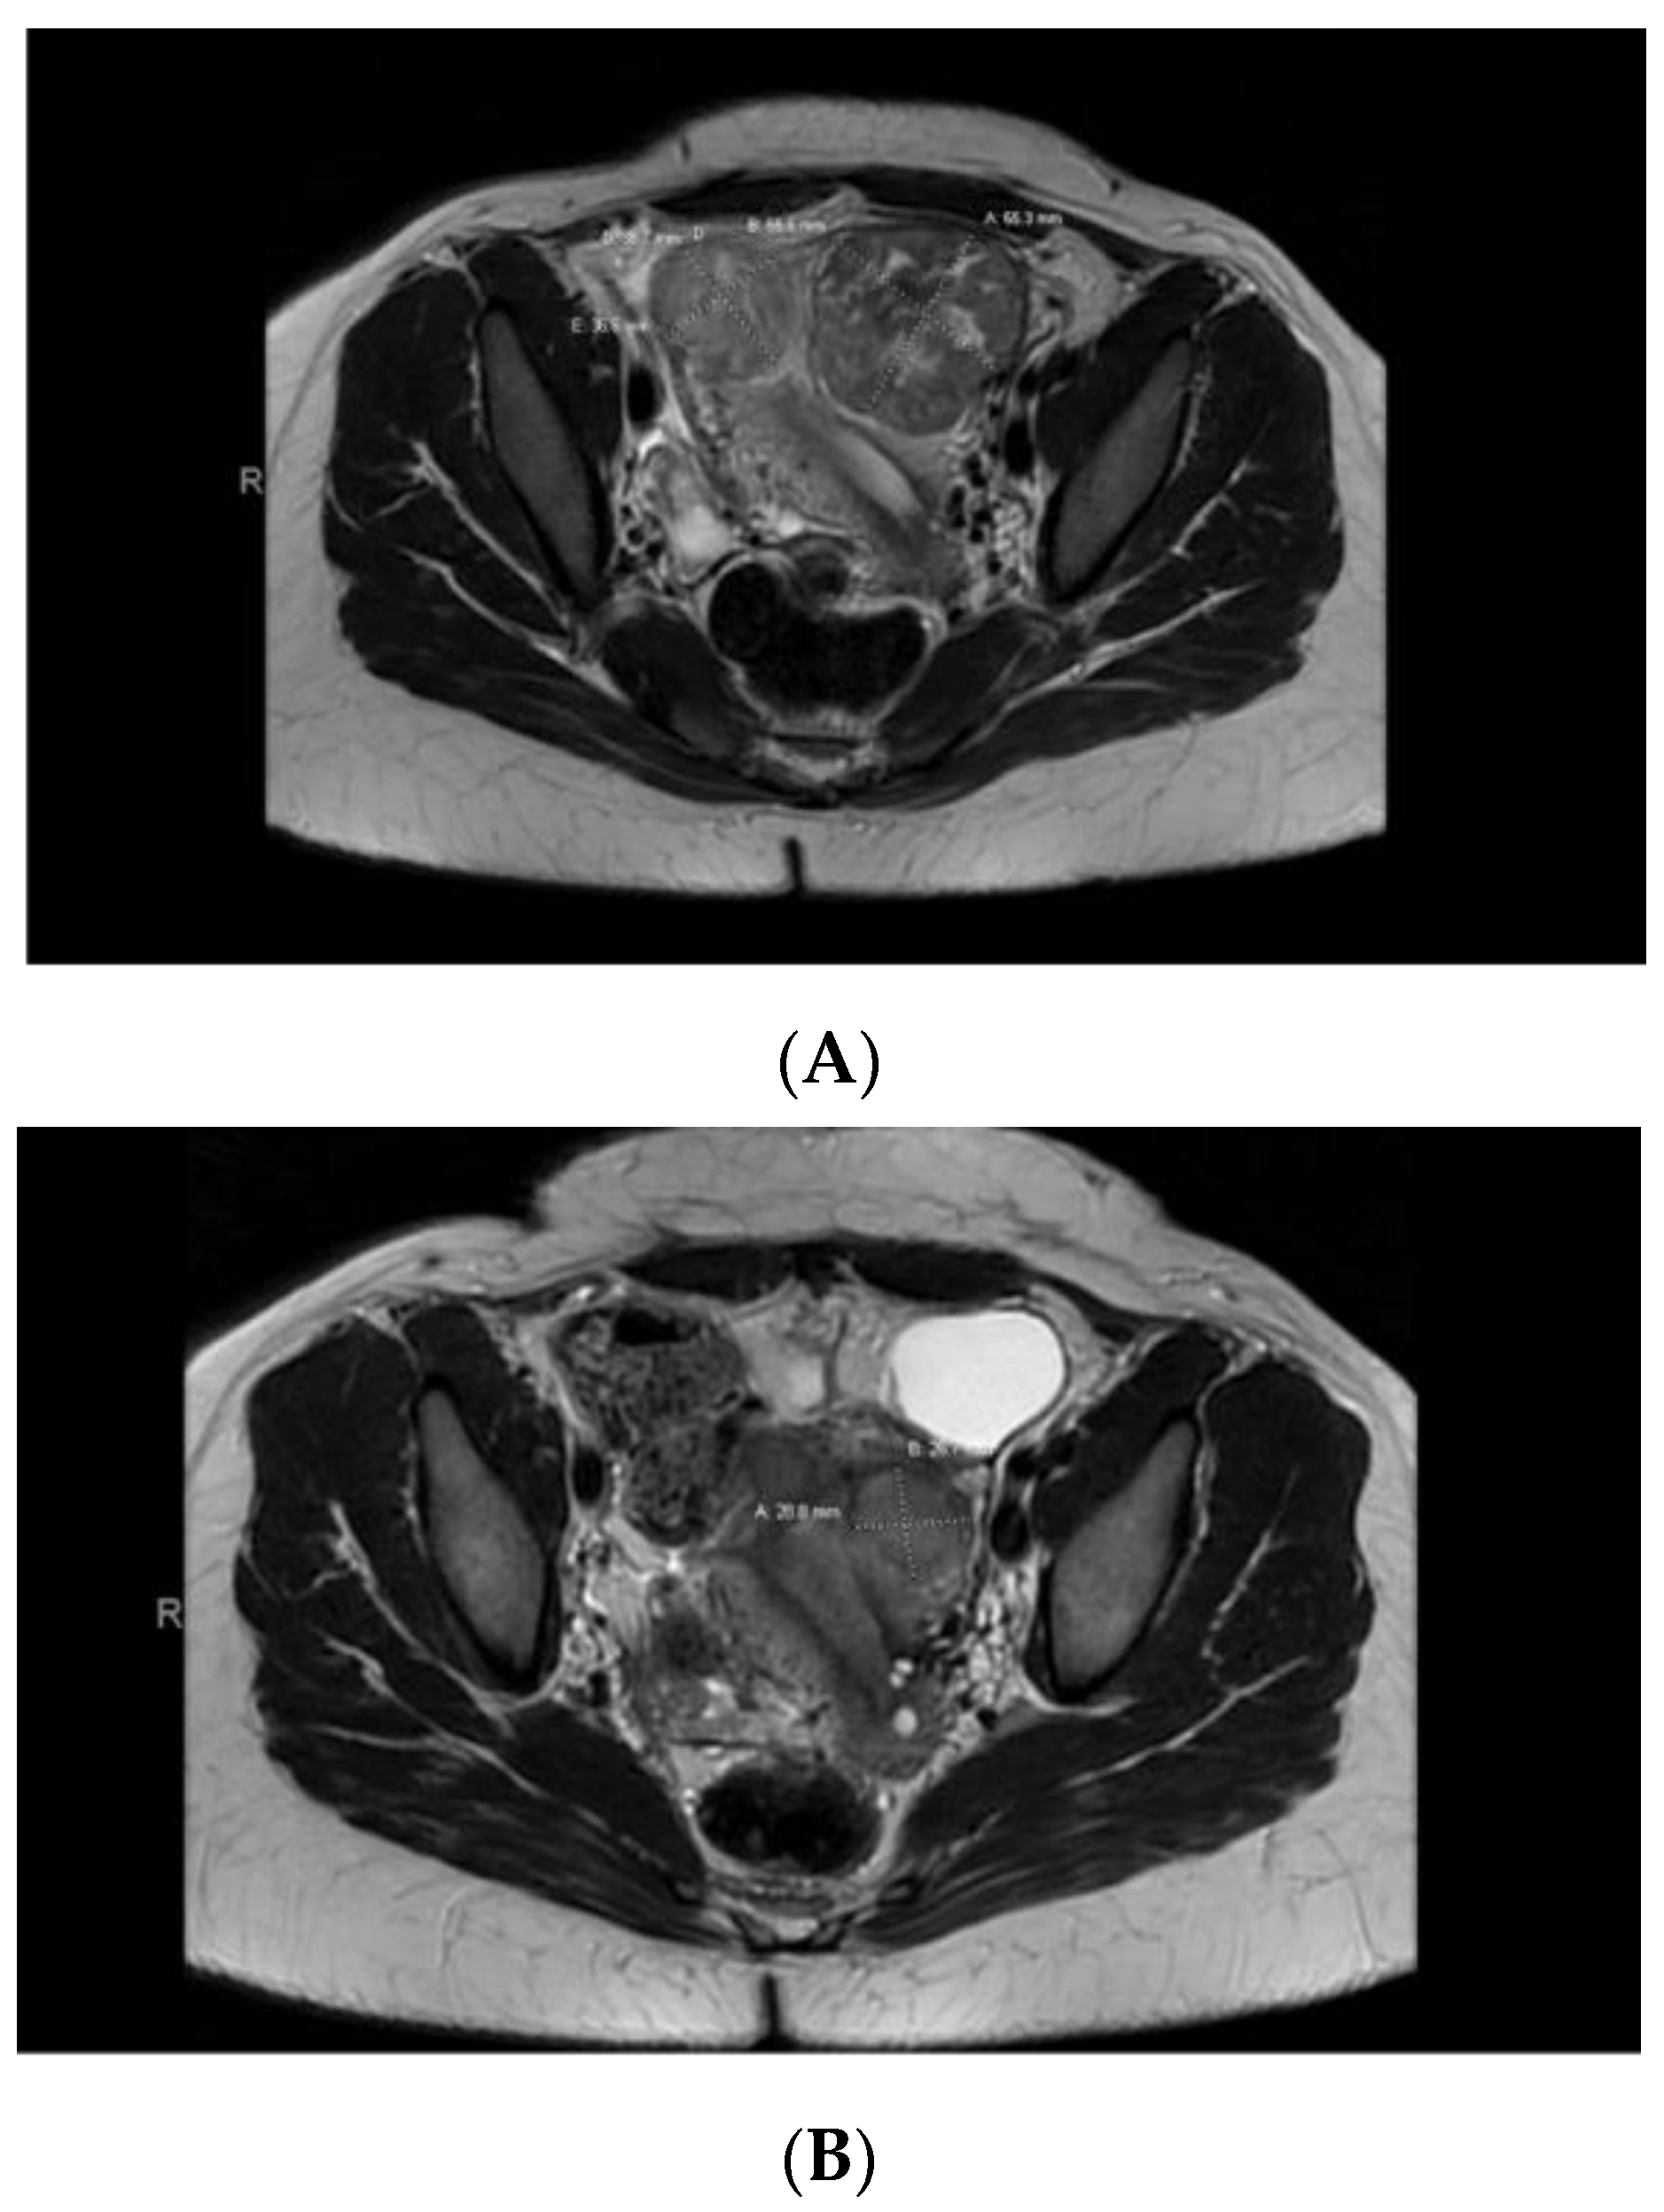

Case 4: A 38-year-old Black patient presented with pelvic pain and heavy menstrual bleeding due to a 10 cm subserosal fundal uterine fibroid (Figure 3). She underwent a robotic hysterectomy with bilateral salpingo-oophorectomy, which confirmed a leiomyoma with features of FH deficiency; germline genetic testing was negative for known pathogenic mutations.

Case 5: A 32-year-old Black patient presented with increased pelvic pressure and urinary frequency. A pelvic ultrasound revealed a 7.5 cm UF and a subsequent pelvic MRI showed a dominant, primarily intramural, anteriorly situated UF measuring approximately 5.6 × 5.5 cm with central degeneration (Figure 4A). AdditionalUFs, including subserosal ones, were noted. The patient underwent a myomectomy with exploratory laparotomy, confirming a leiomyoma with FH deficiency features. Germline genetic testing was positive for a pathogenic mutation in the FH gene, c.239dupA (p.Ile81Aspfs*14). This mutation results in a premature stop codon in exon 2, causing disruption of protein production. A year later, the patient returned with pelvic pain, and a pelvic MRI showed her uterus contained at least 4 fibroids (with a dominant submucosal one), 2 in the right/fundus and 2 on the left (Figure 4B). She chose to undergo a robotic hysterectomy and bilateral salpingectomy, revealing additional FH-d leiomyomas.

Figure 4. (A) Pelvic MRI pre-myomectomy. (B) Pelvic MRI post-myomectomy.